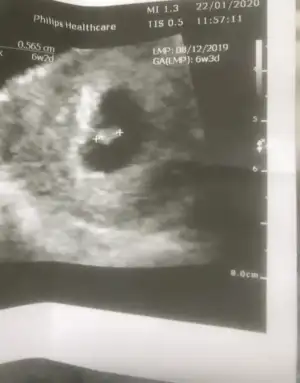

4.3 mm demi kuzum seninkiBebek yokken keseyi bebek varken bebegi olcuyor benimki bu sekilde

Evet bebek 4.3 mm canim4.3 mm demi kuzum seninki

Pek anlamam ama kese şekline göre bir an içimden erkek gibi geçtiBen de bugün gördüm sonunda bebişimi çok şükür.. 6+2 deyiz 5mm miş şuan. Kalp atışını duyamadık ama gördük pıt pıt atıyodu minicik :)

Ne kadarlık peki kuzum hafta olarak benim bebeğim 7+2 de 5mm gözüktü de çok mu küçük acaba diye düşündümEvet bebek 4.3 mm canim

Benim 6+2 de yapildi bu ultrason canim senin gec dollenme olabilir dedin ya sebebi odur belki bilemiyorum kiNe kadarlık peki kuzum hafta olarak benim bebeğim 7+2 de 5mm gözüktü de çok mu küçük acaba diye düşündüm